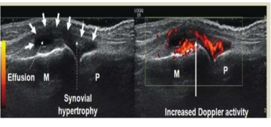

MRI and US can identify synovitis more accurately and have a greater sensitivity in detecting bone erosions than XR - look for soft tissue

joint tenderness, synovitis